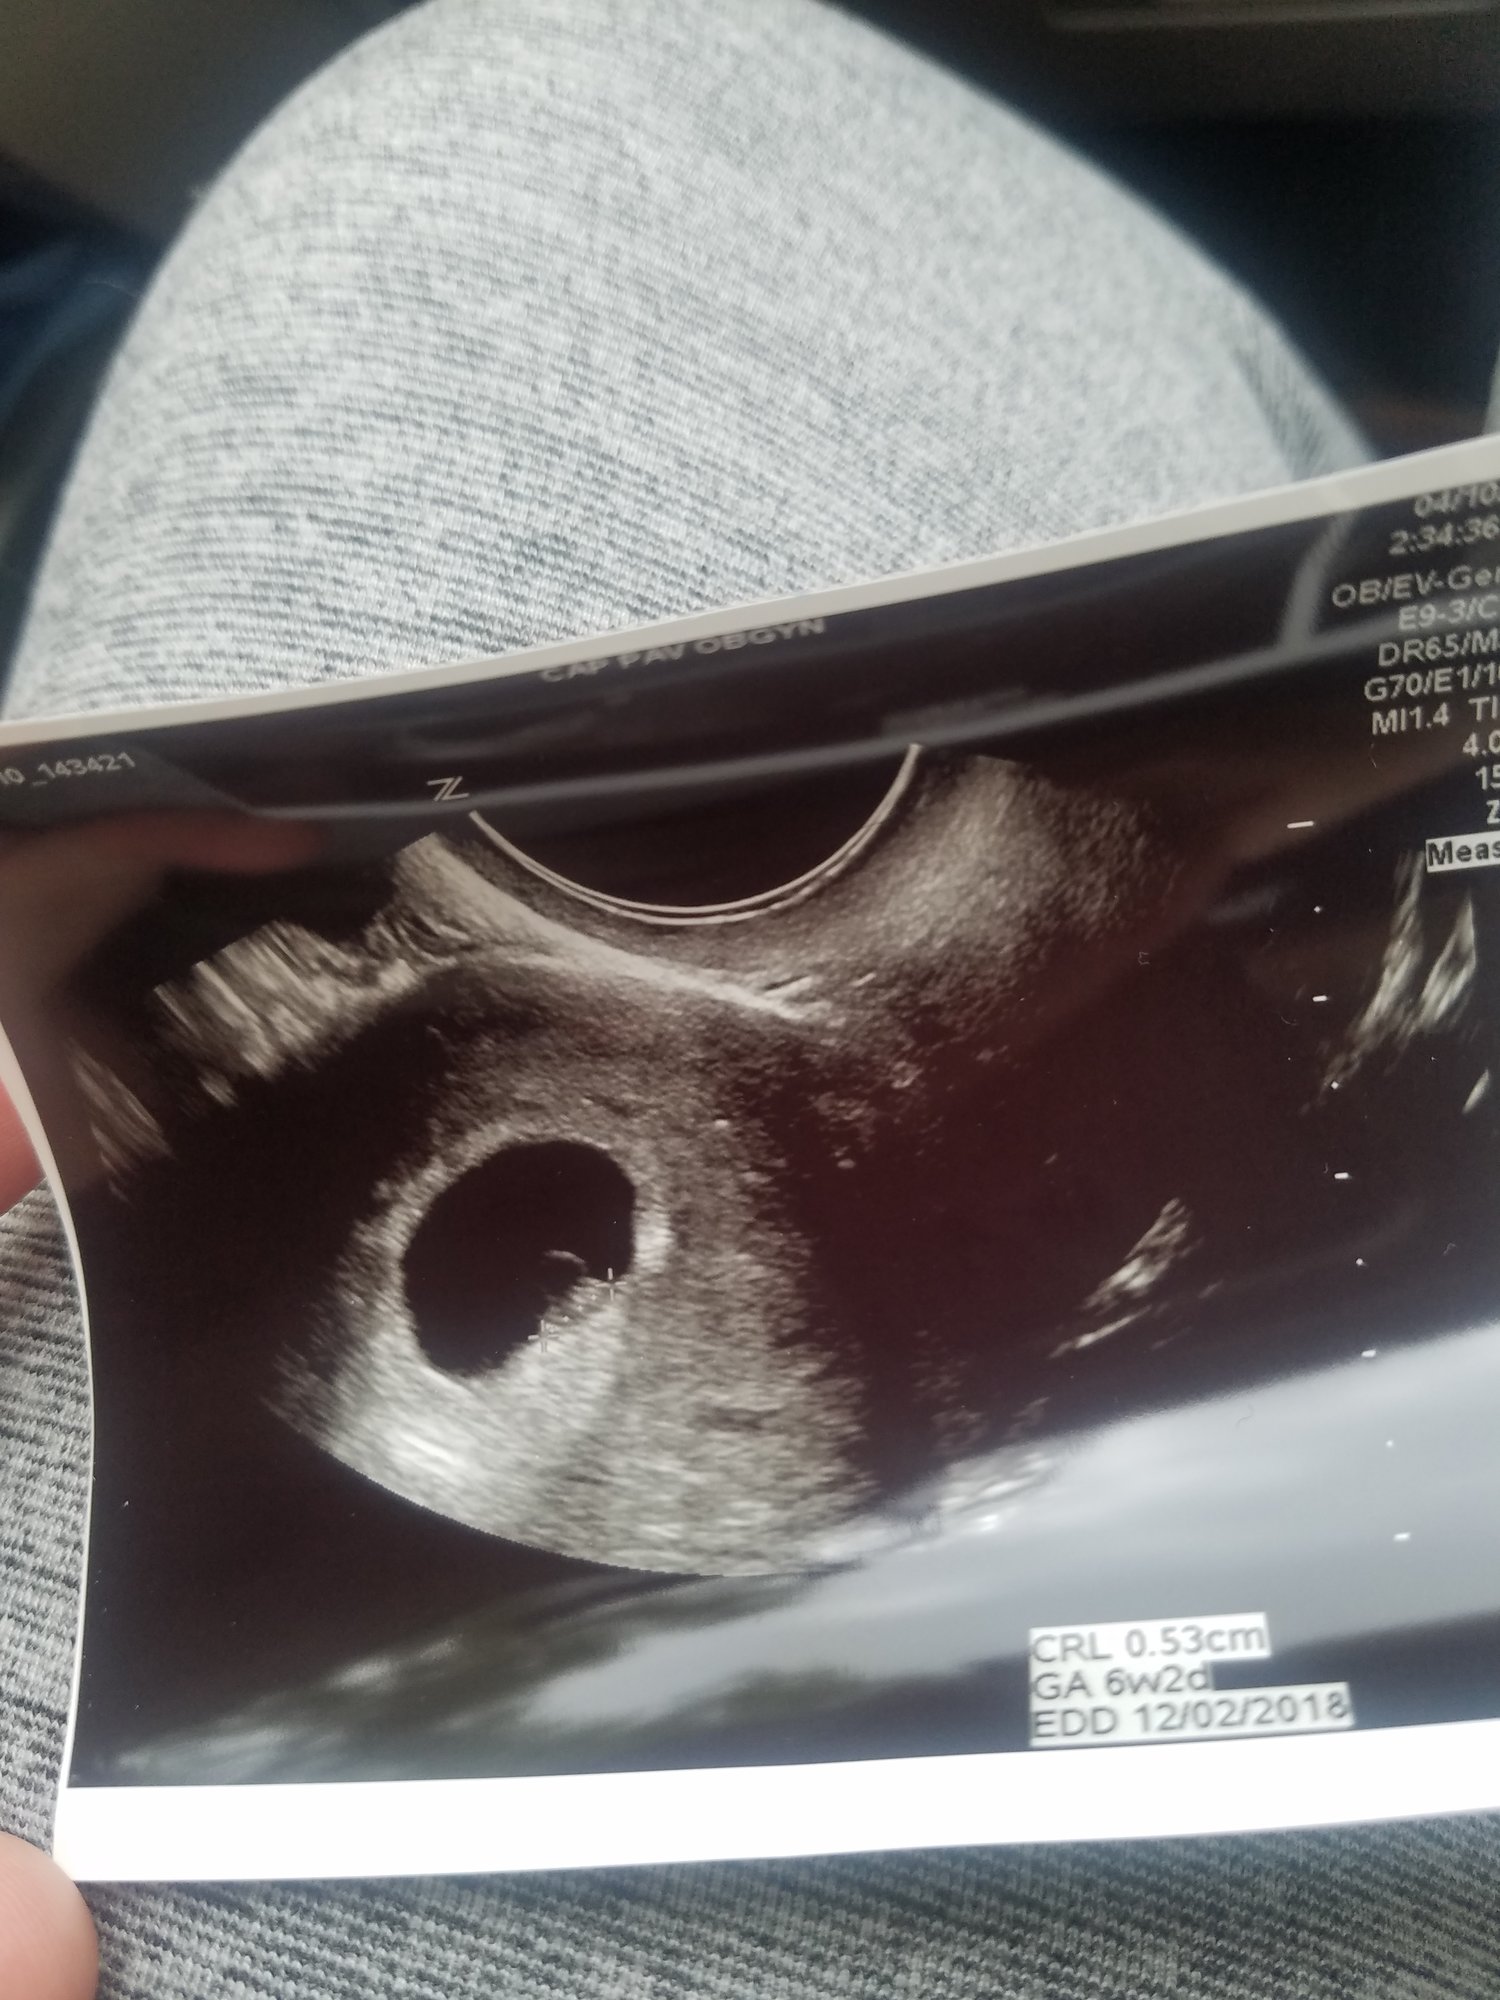

• I had my first ultrasound on Monday! I'm not as far along as I thought - I thought I was past 10 weeks but I'll be just 10 weeks tomorrow. So glad I decided to have an early ultrasound - last pregnancy I just had one at 20 weeks. This time around I was having cramping and bleeding and something seemed off. I guess this is why!!!! Seeing double!! They think identical but can't quite be certain yet as I only wanted an abdominal ultrasound this visit. Needless to say I'm freaking out! New due date of November 8th instead of the 3rd...but I'm sure with twins it may be October!